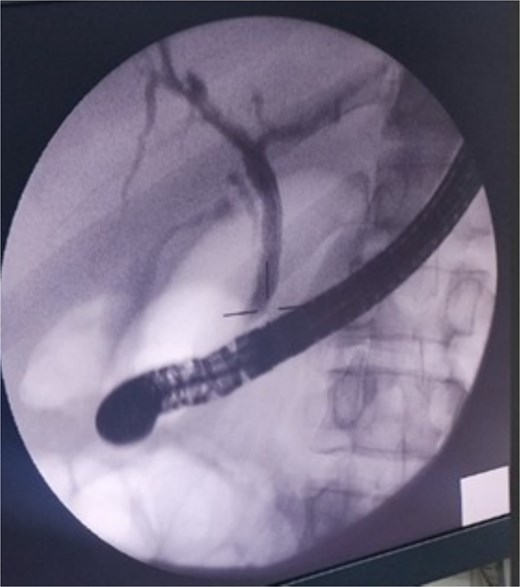

The case was referred to our unit and the decision was made to proceed with ERCP and biliary stenting. During the procedure, the common bile duct and intrahepatic ducts appeared normal. A sphincterotomy was performed, and an 8 Fr, 10Â cm stent was placed in the right hepatic duct (Fig. 3), achieving good bile reflux. No obvious bile leak was detected.

ERCP image showing a normal biliary system. A biliary stent was successfully placed in the right hepatic duct.